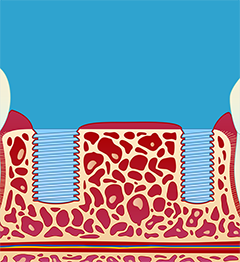

1.) Innsetting av implantat (fikstur) (fig. I-II). Operasjonen utføres under lokalbedøvelse. Etter inngrepet vil man motta mer utfyllende informasjon. Slik vet man hvordan man skal forholde seg i tiden etter operasjonen.

2.) Tilhelingsperiode. Det tar vanligvis 8-12 uker før implantatene kan belastes. Tilhelingsperioden er normalt kortere i underkjeven enn i overkjeven.